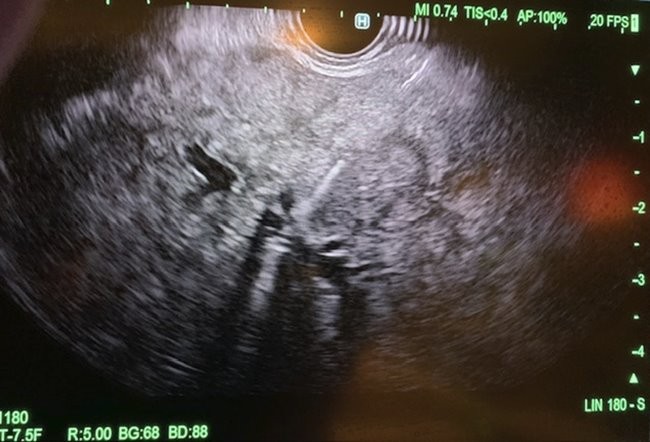

Under general anesthesia, esophagogastroduodenoscopy (EGD) was done using a gastroscope (Olympus America) and there were no esophageal or gastric varices noted. Next, EUS linear array echoendoscope (Olympus America) was passed into the esophagus and advanced into the stomach. The ultrasound image of the liver showed diffuse fatty infiltration. We performed portal pressure gradient using a 25-gauge Cook Echo Tip Insight needle (Cook Endoscopy, Winston Salem, NC). Pulse wave Doppler was used to confirm the middle hepatic vein. From the stomach through the left lobe of the liver, the middle hepatic vein was accessed, and three pressure measurements were taken using digital manometry (Figure 2). The average of 3 measurements from the middle hepatic vein was 17 mmHg. Pulse wave Doppler was used to confirm the left portal vein (Figure 3). Then from the stomach we measured the portal vein pressure by accessing the left portal vein and the average of three measurements was 18 mmHg (Figure 4), giving her a PPG of 1 mmHg. Using Doppler, we ensured there was no bleeding when the needle was withdrawn from both veins (Figure 5 and 6). After the portal pressure gradient measurement, liver core biopsies were done using a 19-gauge Boston Scientific FNB needle (Boston Scientific Marlborough, MA). From the stomach, the left liver lobe was biopsied with the use of EUS to confirm the absence of blood vessels in the needle’s trajectory. One pass and three actuations using the wet heparin technique was performed. The right liver lobe was biopsied from the duodenum and similar methodology was done using the same needle and technique. No bleeding was noted. Both core liver biopsies were sent in formalin to the pathology department for further evaluation.

Figure 4: Needle with manometry placed in the portal vein for acquisition of portal vein pressure accessed via transduodenal, transhepatic approach.